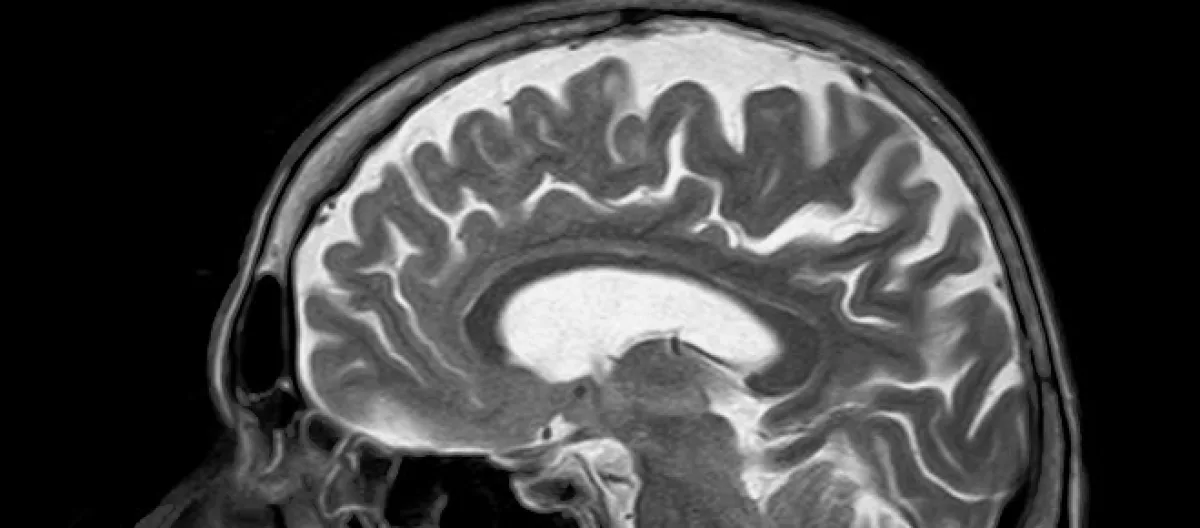

A functional Magnetic Resonance Image (fMRI) is a non-invasive brain scan which shows what parts of the brain are most active by measuring blood flow to those regions. One researcher said, “The first thing that struck us was just how good everyone’s memory was,” because on average they remembered so well that they talked about the episode for almost half as long as the entire episode lasted or more than 20 minutes, even discussing Sherlock’s hat.

But the real surprise was that when they compared the brain images during watching and later during remembering. They were nearly identical; so much so that researchers could identify what scenes the subjects were describing just from comparing the fMRI scan patterns with those taken during the viewing. The researchers also found that everyone’s memory recall process was almost identical, not very individualistic as they had expected, showing that every one of the 22 test subjects remembered in nearly the identical way and organize memories into their personal “mind palaces” in very same patterns. This doesn't mean they all remembered everything exactly the same way - as many tests have shown, eye witnesses seldom agree - rather they all stored their memories in the same parts of the brain in very similar ways and, presumably, how a real Sherlock Holmes would.